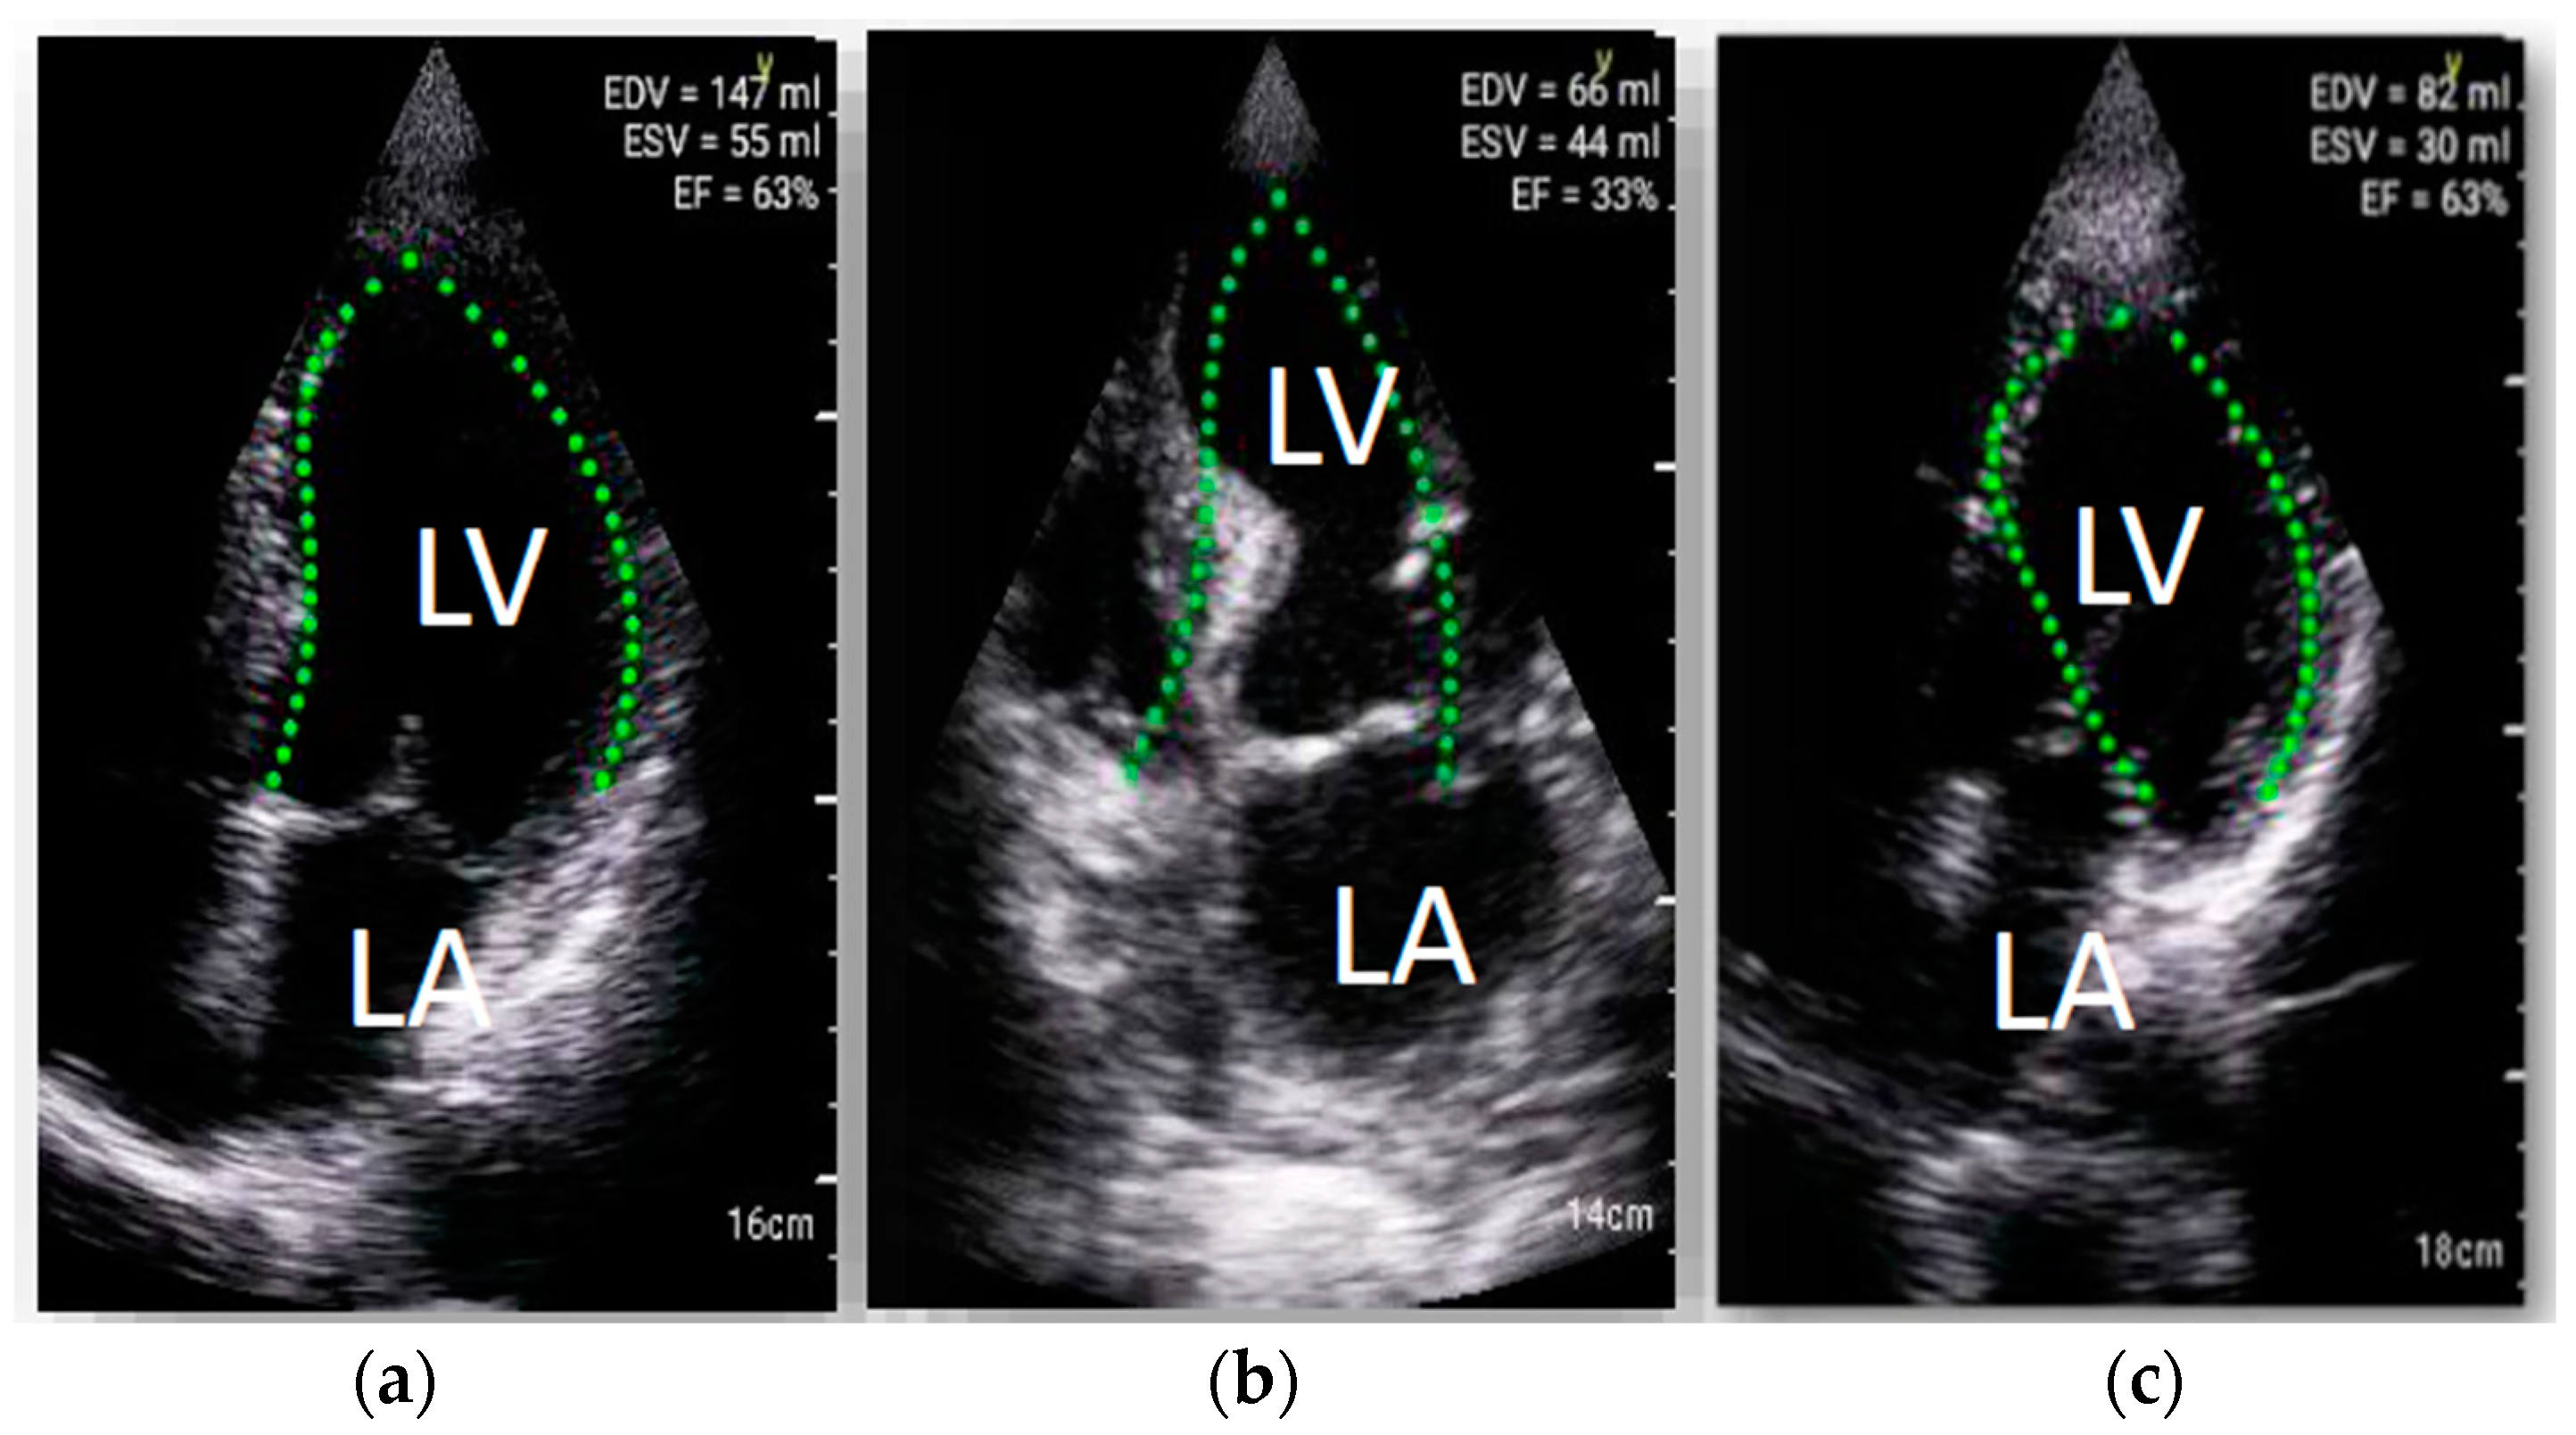

Mean LVEF in standard echocardiography was 46 ± 12%. During HUD examination, automated LV function analysis software failed to calculate LVEF in 29 (46%) cases due to suboptimal image quality (Figure 2). In the remaining cases, the mean value of LVEF was 47 ± 14%. The intraclass correlation coefficient between the LVEF values obtained with LVivo and the reference method was r = 0.84 (p < 0.0001, 95 CI 0.70–0.92). In Bland–Altman analysis, the lower and upper limits of agreement were −12.30 and 17.9, respectively. However, it should be mentioned that in individual cases the plot revealed relatively large discrepancies between both methods of LVEF measurements exceeding 1.96 SD (Figure 3). The feasibility of visual LVEF assessment was 84%. The intraclass correlation coefficient of visual assessment and full standard echocardiography was 0.94 (95% CI: 0.91–0.97).

Figure 2.

Examples of LVivo software implementation in patients with COVID-19; software failed to calculate LVEF in 29 (46%) cases. Four-chamber apical view, (a) successful left ventricle ejection fraction measurements with LVivo software, (b,c) examples of LVivo software failure in endocardial border detection examples of lung ultrasonography performed with HUD.